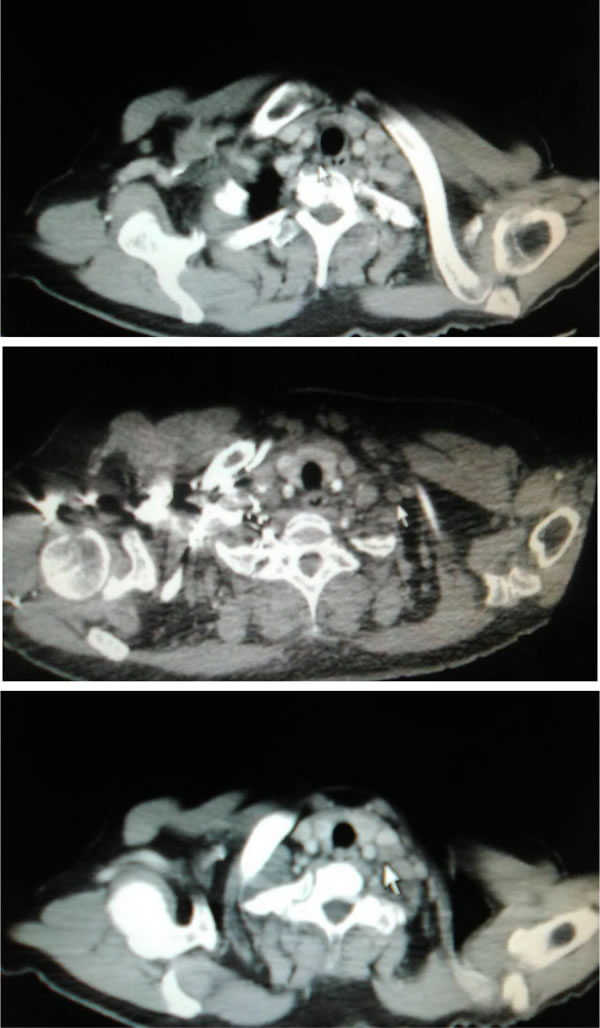

Figure 2: Lymph node metastasis in CTG, MSC and LSC zones, respectively (pointed out by the white arrow).